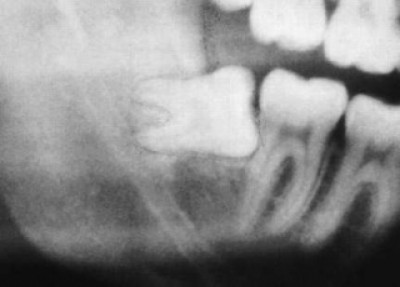

Les dents de sagesse complètement sorties et correctement positionnées posent généralement peu de problèmes. La plupart du temps, l’espace disponible ne suffit pas. Les dents de sagesse décalées (mauvais alignement) ou seulement partiellement sorties causent des dommages au reste de la dentition existante. A l’endroit des avancées, des inflammations de la gencive ou des abcès douloureux peuvent se produire causés par une hygiène buccale rendue difficile. Lors de l’extraction de dents de sagesse profondément ancrées dans l’os, les structures anatomiques voisines, le tissu et les nerfs doivent être épargnées. L’extraction de plusieurs dents de sagesse peut être effectuée en une opération. Les impératifs médicaux définissent combien les dents de sagesse peuvent être enlevées et à quel moment.